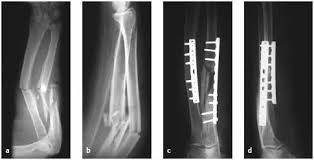

Orthopaedics Home Orthopaedics Orthopedic surgeon studying a x-ray of a broken radius bone in theater after correctional surgery. Man massaging painful wrist on a white background. Pain concept